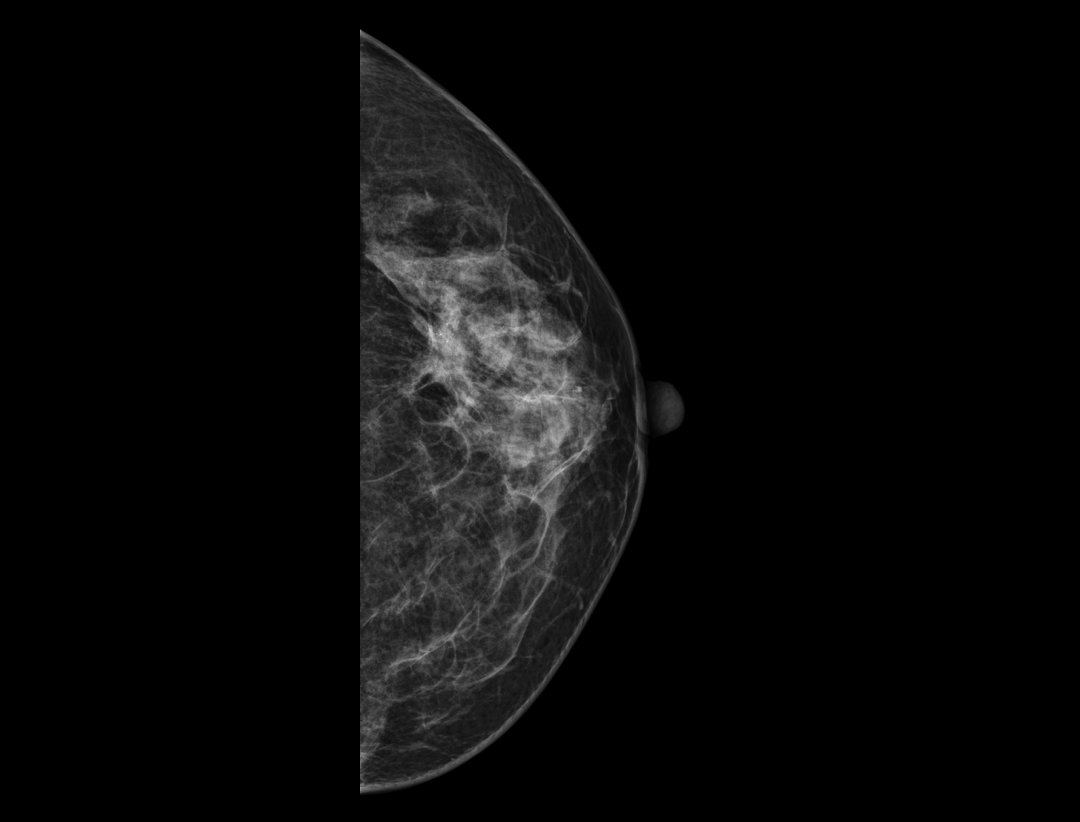

Adaptacyjne dostosowanie grubości warstwy tomosyntezy zapewnia szczegółowe obrazowanie przestrzenne zmian chorobowych i skupisk mikrozwapnień.

Wiele konfiguracji protokołów wyświetlania i wszechstronne narzędzia sprawiają, że przeglądanie mammografii cyfrowej jest bardziej elastyczne i uproszczone. Narzędzie lokalizatora pomaga użytkownikowi wskazać pozycje warstw tomosyntezy wewnątrz obrazu 3D.

Hybrydowe protokoły wyświetlania pozwalają na synchroniczne wyświetlanie obrazów 2D i warstw tomosyntezy w celu łatwego porównania. Dostępne są zarówno pogrubione warstwy (slabs), jak i widok płaszczyzny.